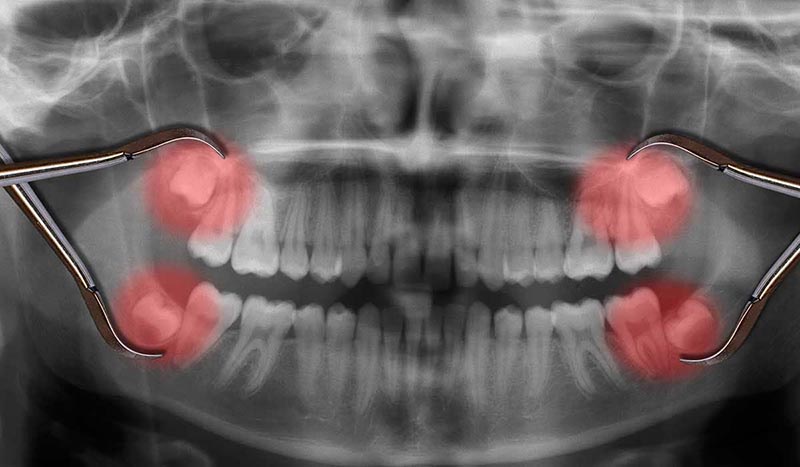

Tooth Extraction and The Aftercare